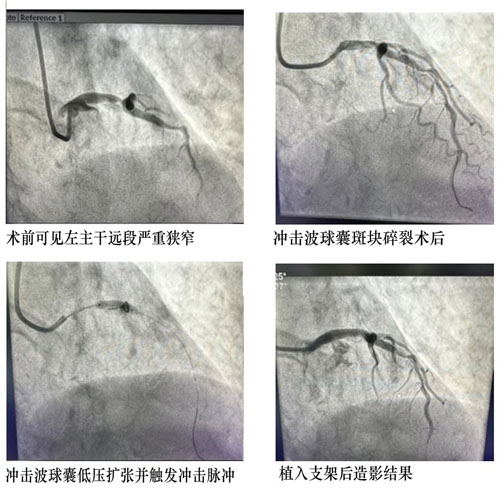

近日,我院心血管內(nèi)科獨立完成本地區(qū)首例冠脈血管內(nèi)沖擊波球囊斑塊碎裂術(shù)。

患者,男,80歲,1個月前因胸痛收住院。冠脈造影提示左主干至前降支鈣化病變導(dǎo)致80-90%狹窄,右冠脈閉塞?;颊吖诿}病變嚴(yán)重,手術(shù)風(fēng)險較高,先期開通閉塞右冠病變并植入支架治療,此次處理左主干病變。

患者年齡大,左主干重度狹窄并嚴(yán)重鈣化,常規(guī)PTCA(經(jīng)皮冠狀動脈腔內(nèi)血管成形術(shù))難以充分處理病變,可能導(dǎo)致支架無法順利通過、膨脹不全等風(fēng)險。心血管內(nèi)科CCU討論后決定應(yīng)用沖擊波球囊,選擇3.5×12mm Shockwave球囊精確定位于LM-LAD鈣化病變嚴(yán)重處,根據(jù)標(biāo)準(zhǔn)操作流程,4ATM低壓力擴(kuò)張球囊,累計觸發(fā)2個周期的沖擊波鈣化斑塊碎裂術(shù),利用聲波壓力震碎血管壁內(nèi)鈣化沉積,解決了嚴(yán)重鈣化病變普通球囊無法充分?jǐn)U張的難題,復(fù)查冠脈造影見鈣化病變狹窄明顯減輕。經(jīng)1小時手術(shù)治療,成功植入藥物支架1枚,解除血管狹窄,患者未再有癥狀,順利出院。

冠狀動脈嚴(yán)重鈣化可使冠狀動脈介入治療的難度和風(fēng)險成倍增加,更容易發(fā)生支架血栓形成和再狹窄等不良結(jié)果。冠脈血管沖擊波球囊斑塊碎裂術(shù)通過聲壓力波作用于冠狀動脈內(nèi)膜及中膜下的鈣化病灶,使鈣化松解卻不影響血管內(nèi)膜,將鈣化病變震裂,使血管恢復(fù)彈性,為后續(xù)支架的置入提供更理想的管腔,原理簡單,操作方便,并且安全性良好。

此次心血管內(nèi)科獨立完成本地區(qū)首例冠脈血管內(nèi)沖擊波球囊斑塊碎裂術(shù),代表我院冠脈介入治療面對鈣化病變有了新的強(qiáng)力武器,為患者提供更全面的治療方案。(田濟(jì)源)